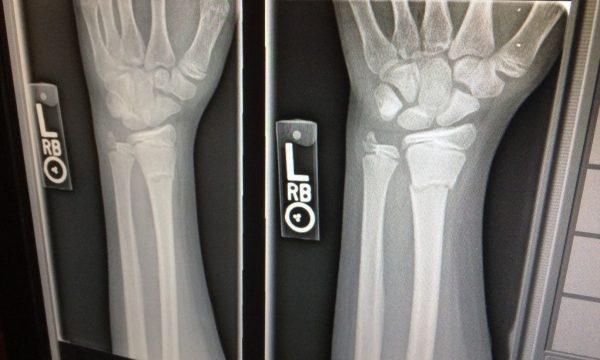

Za uspešno zdravljenje je ključna natančna diagnoza. Ta temelji na kliničnem pregledu in po potrebi slikovni diagnostiki, kot sta rentgen ali magnetna resonanca.